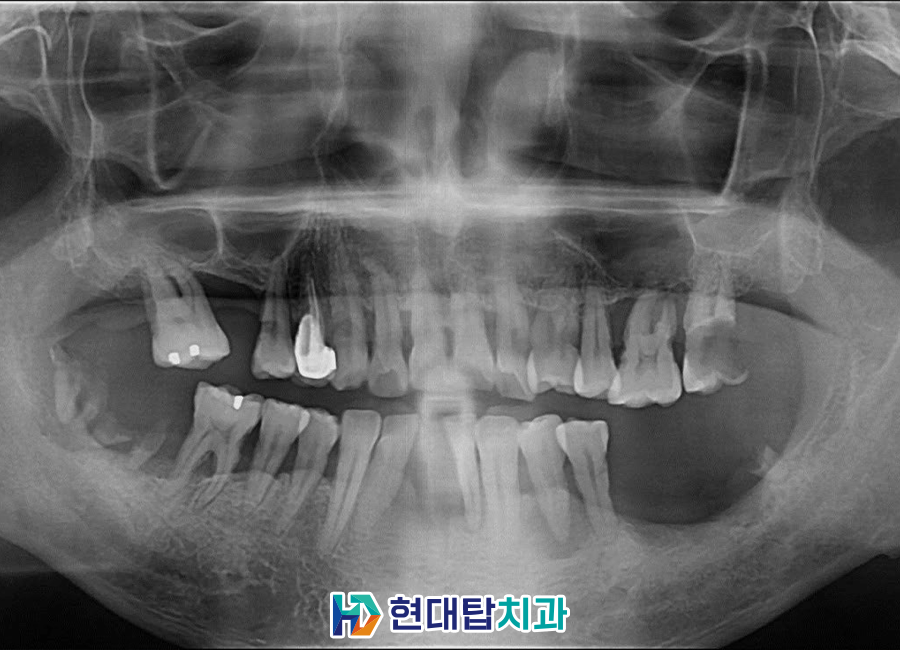

본 환자분은 50세 남성 환자분으로

본원에 내원 중이신 환자분의 소개로

내원해 주셨습니다.

전체적으로 잇몸뼈의 소실이 크셨고

아래 앞니는 많이 흔들려서 저절로

발치가 된 상태로

전반적인 치아의 상실과

충치, 치주 질환, 잇몸 염증으로 인해

잇몸뼈의 상태가 많이 좋지 않으셨습니다.

처음 내원해 주셨을 때 촬영한

구강 내 사진입니다.